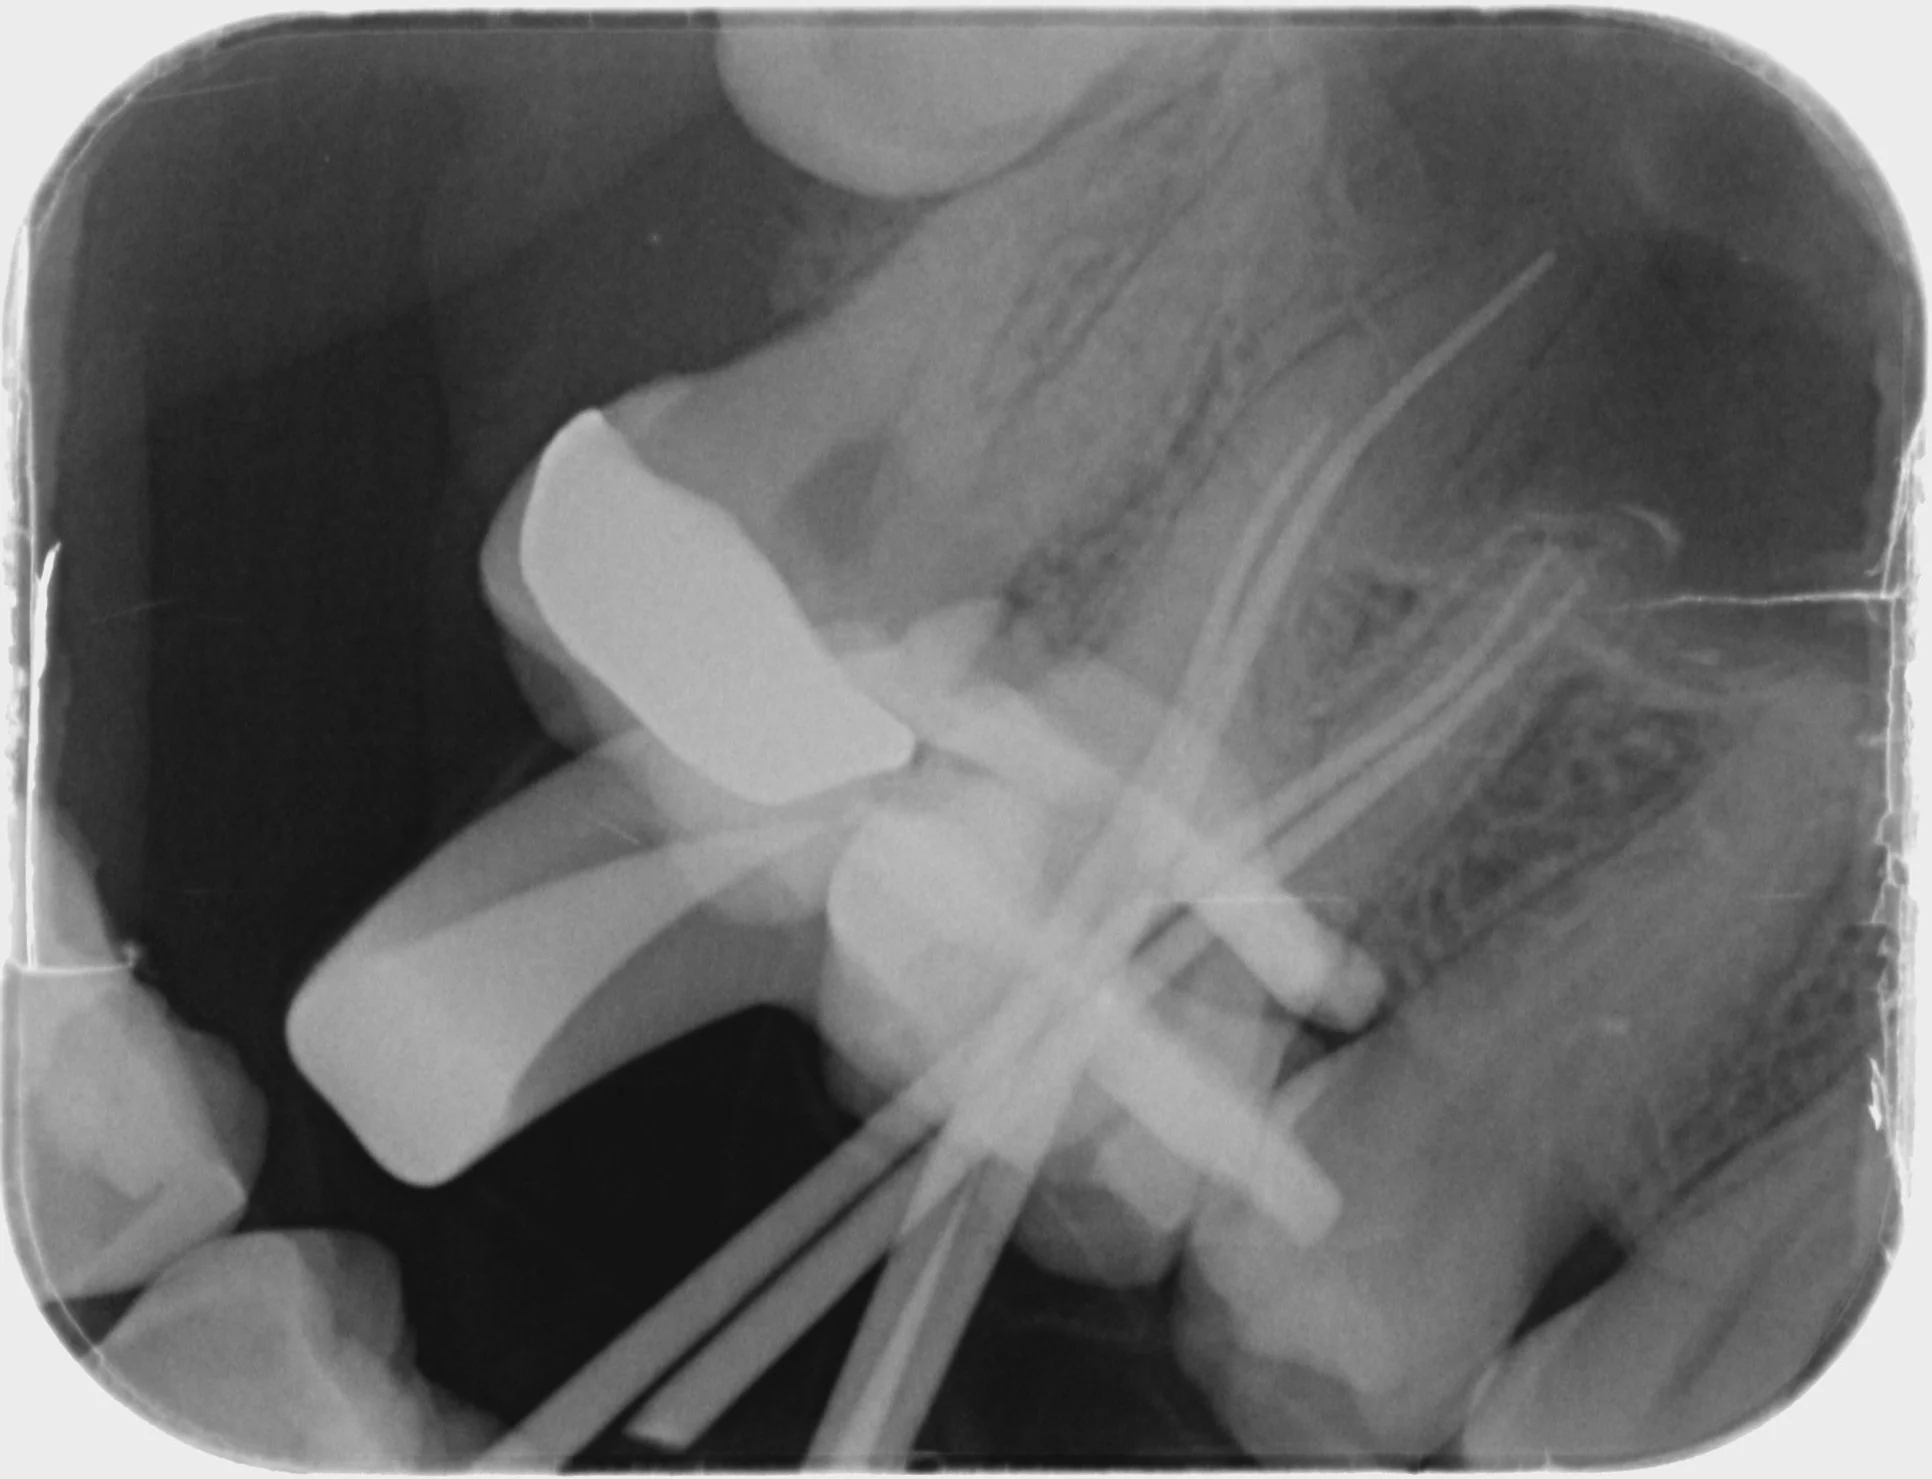

Endodontics